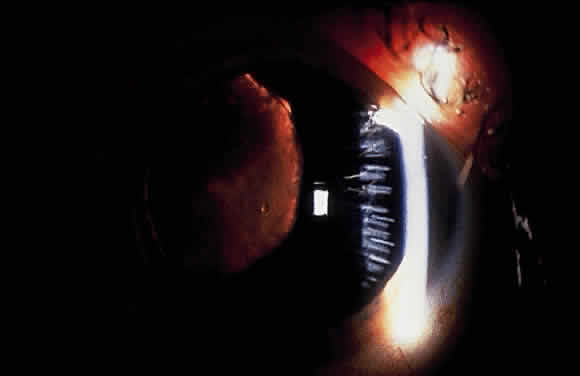

Problems during lens extractions in patients with XFS have been well described in the literature. Early reports note an increased incidence of intraoperative lens dislocation, vitreous loss, and capsular rupture in eyes with XFS undergoing intracapsular cataract extraction.144–146 Dark observes that synechia formation between the iris pigment epithelium and the peripheral anterior lens capsule can lead to capsular rupture during the intracapsular procedure.142 With extracapsular cataract extraction, several surgeons report an increased risk of zonular and capsular breaks in exfoliation eyes143,147–150 (Fig. 13). Guzek and coworkers, for example, report that the risk of zonular breaks in 241 patients with XFS during extracapsular cataract extraction was four times greater than in 736 non-XFS patients.148 Similarly, an increased frequency of intraoperative complications has been observed in exfoliative eyes undergoing phacoemulsification. Scorolli and associates found the risk of complications to be about five times greater when XFS was present.151 Droslum and coworkers note a 9.6% incidence rate of capsular tears, zonular tears, or vitreous loss during phacoemulsification procedures in XFS eyes compared with a 3.7% rate of the same complications in non-XFS cases.152

Fig. 13. Inferior and superior zonular dialyses that occurred during extracapsular cataract extraction in patient with exfoliation syndrome. (Skuta GL, Parrish RK II, Hodapp E et al: Zonular dialysis during extracapsular cataract extraction in pseudoexfoliation syndrome. Arch Ophthalmol 105:633, 1987)

The increased frequency of zonular breaks in exfoliative patients undergoing cataract procedures is believed to be primarily caused by degeneration of the zonular fibers.47,153 Other factors contributing to complicated cataract surgery in eyes with XFS include poor pupillary dilation150,153,154 and, as noted previously, synechiae between the iris pigment epithelium and anterior lens capsule.142